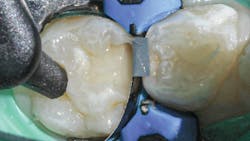

Once preparation and removal of the infected dentin is achieved, a sectional matrix and ring system (Composi-Tight 3D XR, Garrison Dental Solutions) is used. Taking particular care at the gingival margin, proper matrix placement will ensure control over leakage and any possible contamination, which is important for long-term success (figure 2).

A selective-etch technique with 35% phosphoric acid is used to achieve the highest possible bond strengths.6,7 The etchant is washed and the tooth is dried without desiccating it. A universal bonding agent (Futurabond U, Voco) is rubbed onto the tooth surface for 20 seconds (figure 3), and thenThis is a modified snowplow technique, in which the flowable base layer is light cured in combination with placement of 4 mm of the restorative material.8,9 This allows the flowable to extrude up to the occlusal surface and down to the gingival margins, filling any voids.